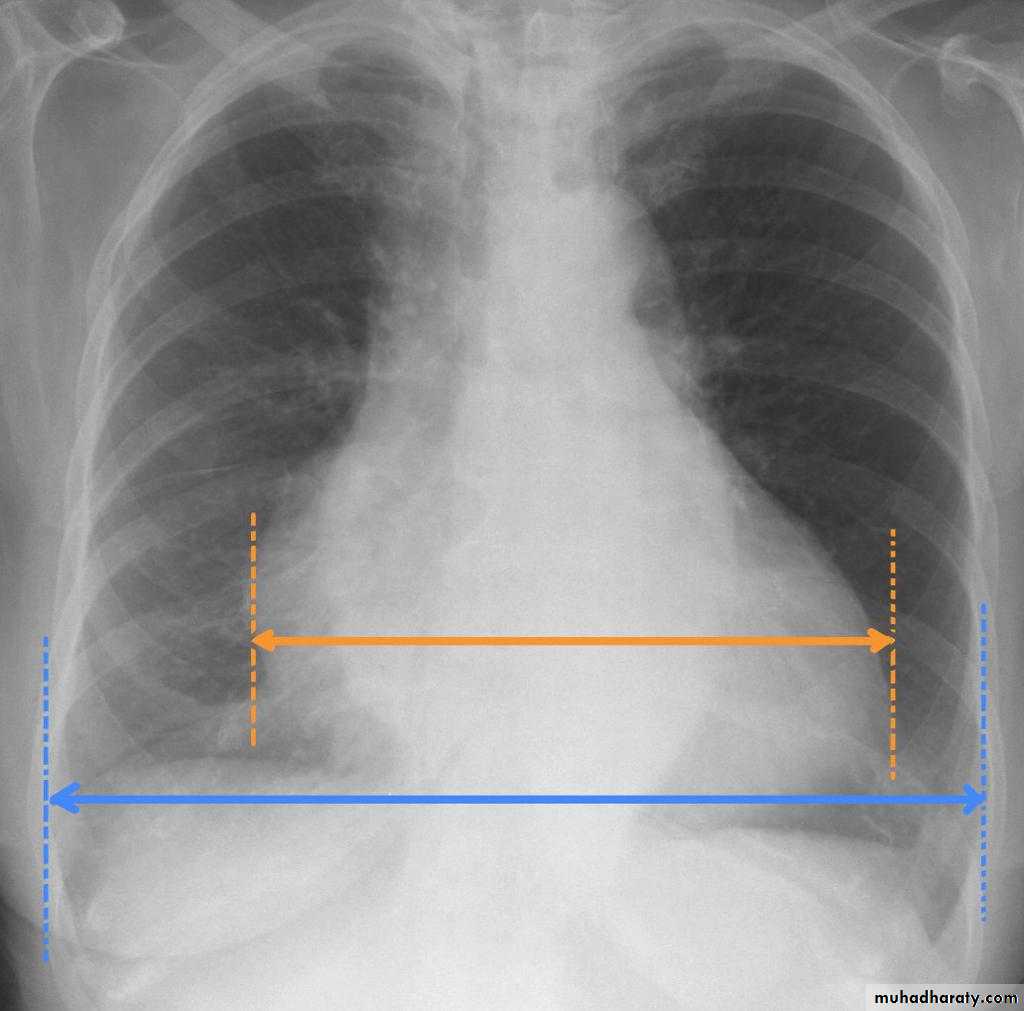

Upper zone>>>> 1st and 2nd ribsMiddle zone>>>> 3rd and 4th ribsLower zone>>>> 5th and 6th ribsHow to asses cardiac size We take 2 lines the between borders of cardiac shadow and 2 lines between the inner surface of thoracic cage and the ribsCardiothoracic ratio (CTR) =Cardiac Width : Thoracic WidthA CTR of greater than 1:2 (50%) is considered abnormal.